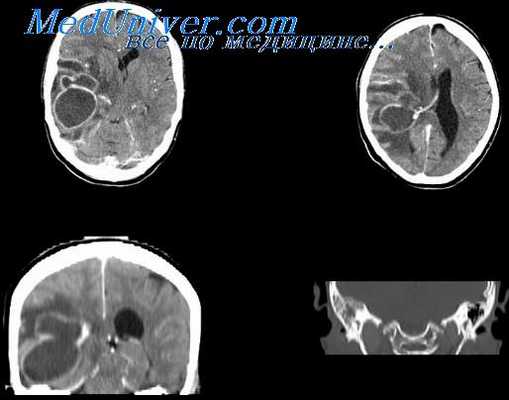

МРТ при абсцессе височной доли мозга

Точность диагностирования с помощью КТ головного мозга зависит от стадии формирования абсцесса. На ранних стадиях заболевания диагностика затруднена. На этапе раннего энцефалита (1-3 сутки) КТ определяет зону сниженной плотности неправильной формы. Введенное контрастное вещество накапливается неравномерно, преимущественно периферических отделах очага, реже в центре.

На более поздних этапах энцефалита контуры очага приобретают ровные округлые очертания. Контрастное вещество распределяется равномерно, по всей периферии очага; плотность центральной зоны очага при этом не меняется. Однако на повторной КТ (через 30-40 минут) определяется диффузия контраста в центр капсулы, а также наличие его и в периферической зоне, что не характерно для злокачественных новообразований.

Инкапсулированный абсцесс мозга на КТ имеет вид округлого объемного образования с четкими ровными контурами повышенной плотности (фиброзная капсула). В центре капсулы зона пониженной плотности (гной), по периферии видна зона отека. Введенное контрастное вещество накапливается в виде кольца (по контуру фиброзной капсулы) с небольшой прилежащей зоной глиоза.

На повторной КТ (через 30-40 минут) контрастное вещество не определяется. При исследовании результатов компьютерной томографии следует учесть, что противовоспалительные препараты (глюкокортикостероиды, салицилаты) в значительной степени влияют на скопление контраста в энцефалитическом очаге.

МРТ головного мозга — более точный метод диагностирования. При проведении МРТ на первых стадиях формирования абсцесса мозга (1-9 сутки) энцефалитический очаг выглядит: на Т1-взвешенных изображениях — гипоинтенсивным, на Т2-взвешенных изображениях — гиперинтенсивным. МРТ на поздней (капсулированной) стадии абсцесса головного мозга: на Т1-взвешенных изображениях абсцесс выглядит, как зона пониженного сигнала в центре и на периферии (в зоне отека), а по контуру капсулы сигнал гиперинтенсивный. На Т2-взвешенных изображениях центр абсцесса изо- или гипоинтенсивный, в периферической зоне (зоне отека) гиперинтенсивный. Контур капсулы четко очерчен.